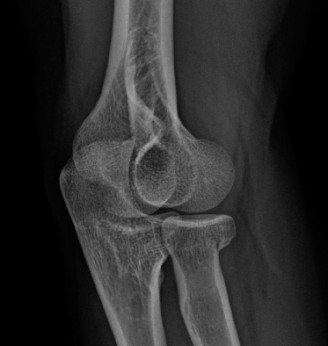

Treat a patient with scapular winging? CASE 23 A 47-year-old, right-hand-dominant male presents to your clinic complaining of right shoulder weakness for the past 2 months. He denies any history of trauma but notes sudden onset of pain 2 months ago that lasted approximately 2 weeks and then subsided without any intervention and was followed by shoulder weakness. He works as a lawyer and has been going through a divorce for the past year. Physical examination reveals no tenderness to palpation about the shoulder. He has decreased sensation over the lateral aspect of the shoulder, decreased muscle bulk over the left shoulder compared with the contralateral side, and weakness with left shoulder abduction. He is distally neurovascularly intact. The patient had already been referred for an x-ray and MRI by his primary care doctor that are shown in Figures 2–62 and 2–63.

Figure 2–62

Figure 2–63

The correct answer is (C). The patient’s decreased sensation over the deltoid, deltoid muscle atrophy on examination, and MRI with atrophy of the teres minor points to axillary nerve dysfunction. Suprascapular nerve injury (Choice A) would result in atrophy of the infraspinatus and or infraspinatus muscles, leading to weakness with external rotation and/or forward flexion. Dorsal scapular nerve injury (Choice B) would result in weakness of the rhomboid muscles and levator scapulae. While injury to the posterior cord of the brachial plexus (Choice D) would result in symptoms of axillary nerve palsy, they would also involve dysfunction of the radial nerve, which also comes off the posterior cord.